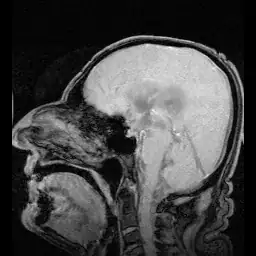

The image in the OP's question is of a patient with normal pressure hydrocephalus (NPH) showing pulsations of CSF with heartbeat, nothing more.

MRI showing pulsation of CSF